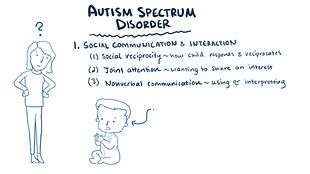

Diagnosis

Diagnosis is based on behavior, not cause or mechanism.[24][111] Under the DSM-5, autism is characterized by persistent deficits in social communication and interaction across multiple contexts, as well as restricted, repetitive patterns of behavior, interests, or activities. These deficits are present in early childhood, typically before age three, and lead to clinically significant functional impairment. Sample symptoms include lack of social or emotional reciprocity, stereotyped and repetitive use of language or idiosyncratic language, and persistent preoccupation with unusual objects. The disturbance must not be better accounted for by Rett syndrome, intellectual disability or global developmental delay.[3] ICD-10 uses essentially the same definition.[19]